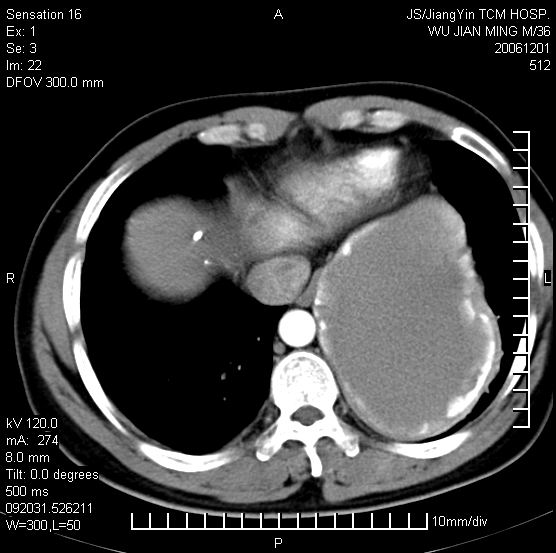

以下是引用dyqct在2006-12-1 21:17:00的发言:[br]左心缘旁及后肋膈窦区见巨大椭圆形混杂密度肿块,周围见大小不等斑片状钙化,内部无强化,周围包膜轻度强化,心脏明显受压变形,即明显占位效应,肿块广基与心包、膈相连。肝、脾内、肝门见多数小结节状钙化影。[br]考虑:1、左心缘旁及后肋膈窦区慢性包裹性胸膜炎(结核性);[br] 2、肝、脾及肝门淋巴结核已钙化。[br]

以下是引用zrs在2006-12-2 17:28:00的发言:[br]肺内、肝脾内虽有钙化,但不支持结核性胸胸膜炎包裹,而支持寄生虫感染![br][br]

以下是引用zyx168在2006-12-2 10:10:00的发言:[br][br]肝脾肺内多发钙化灶